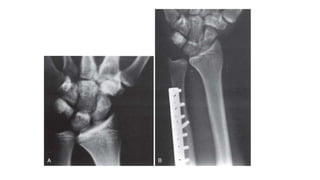

Ulnar shortening osteotomy

Ulnar impaction andDRUJ arthritis • Non operative • Operative 1. Without DRUJ arthritis • Arthroscopic joint debridement • Open/arthroscopic distal ulnar resection • Ulnar shortening osteotomy 2. With DRUJ Arthritis • Excisional or interposition arthroplasty • Modified arthrodesis

• #34 Type 2 with pos UV more than 2mm, App- plate- mark- osteotomy- interfrag-plate fixation

• #35 Ulnar shortening osteotomy. A, Wrist of 16-year-old male wrestler with bilateral ulnar wrist pain and positive ulnar variance of 2 mm. B, Four weeks after surgery, wrist is in ulnar neutral variance and osteotomy is healed.